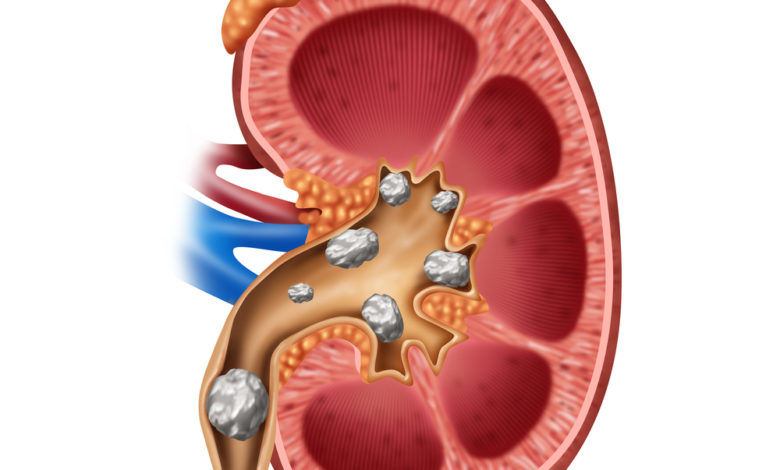

Doğum sancısından bile şiddetli ağrılara neden olabilen böbrek taşları ülkemizde her yıl erkeklerin yüzde 12’sinin, kadınların da yüzde 6’sının kapısını çalıyor. Acıbadem Fulya Hastanesi Üroloji Uzmanı Prof. Dr. Sinan Zeren hastaların hayatını adeta kabusa çevirebilen böbrek taşlarının günümüzde uygun tedavilerle, açık cerrahilere gerek kalmadan tedavi edilebildiğine dikkat çekerek, “Ancak toplumda doğru sanılan hatalı bilgiler nedeniyle hastalar hekimlere başvurmakta gecikebiliyor veya taş tanısı konulmuş olsa bile tedavi sürecindeki ihmaller yüzünden ciddi ve kalıcı böbrek fonksiyon kayıpları ile karşılaşabiliyorlar. Dolayısıyla özellikle daha önceden idrar yollarından taş veya kum dökmüş ya da ameliyat geçirmiş olan hastalar benzer rahatsızlıkları hissettiklerinde geç kalmadan hekime başvurmalı” diyor. Acıbadem Fulya Hastanesi Üroloji Uzmanı Prof. Dr. Sinan Zeren, böbrek taşları hakkında toplumda doğru sanılan yanlış bilgileri anlattı, önemli öneri ve uyarılarda bulundu.

Yanlış: Böbrek taşları mutlaka ağrı yapar

Doğrusu: Toplumdaki yaygın inanışın aksine, böbrek içinde kenarda duran taş, idrarın böbrekten çıkışına engel olmadığı sürece, iri boyutta bile olsa (hatta böbreğin tamamını dolduran taşlar dahil) hiç ağrı yapmayabiliyor. Eğer taş böbrek çıkışına gelip tıkarsa veya böbrekten çıkıp mesaneye inen kanalın içine girerse, ağrı oluşabiliyor. “İdrar yollarının aniden ve tümüne yakın oranda tıkanması ise genellikle çok şiddetli ağrıya yol açıyor” diyen Üroloji Uzmanı Prof. Dr. Sinan Zeren sözlerine şöyle devam ediyor: “Ağrının nedeni, taşın idrar yolunu tıkaması sonucunda gerisindeki idrar yollarının içinde artan basınç ve buna bağlı idrar yolu duvarlarının gerilmesidir. İdrar yolunu tıkamayan taş ise ciddi bir ağrıya neden olmuyor.”